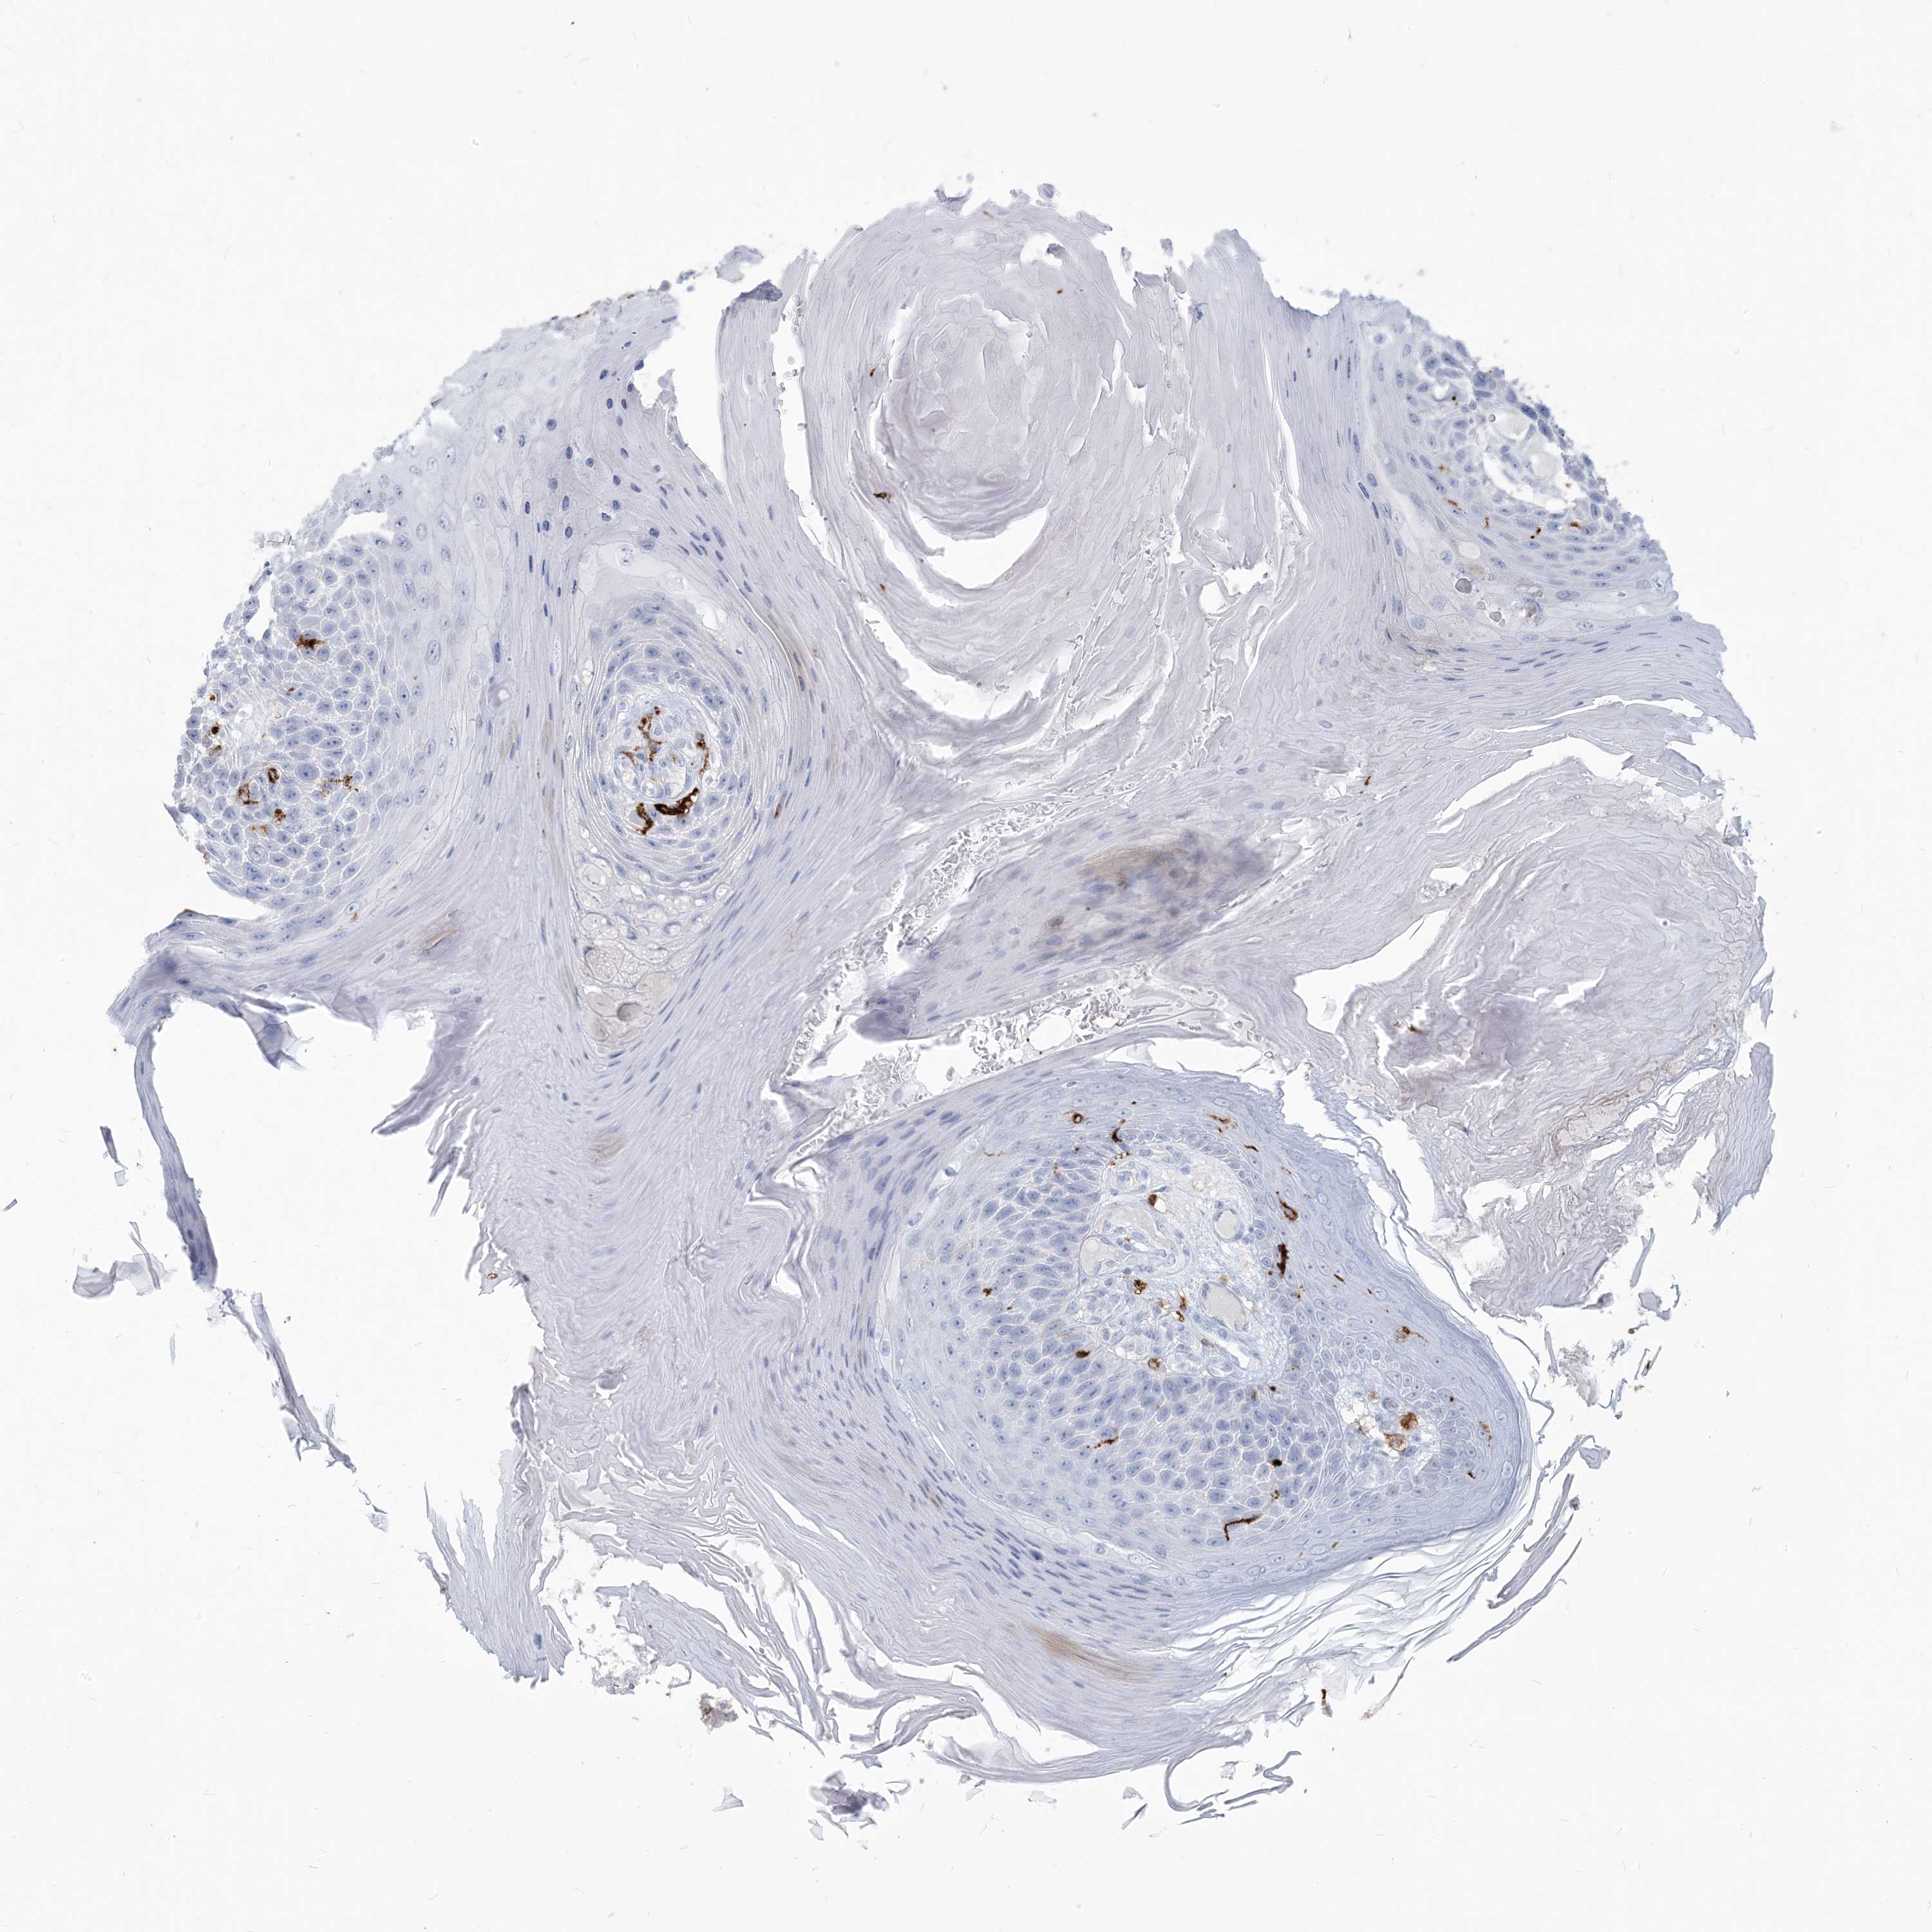

SKIN CANCER - Protein expressioni

A mouse-over function shows sample information and annotation data. Click on an image to view it in a full screen mode. Samples can be filtered based on level of antibody staining by selecting one or several of the following categories: high, medium, low and not detected. The assay and annotation is described here.

Each image is clickable and will lead to virtual microscopy that enables deeper exploration of all samples and also displays staining intensity scores, fraction scores and subcellular localization as well as patient and tissue information for each sample.

Antibody CAB015400

Squamous cell carcinoma, NOS

Squamous cell carcinoma in situ, NOS